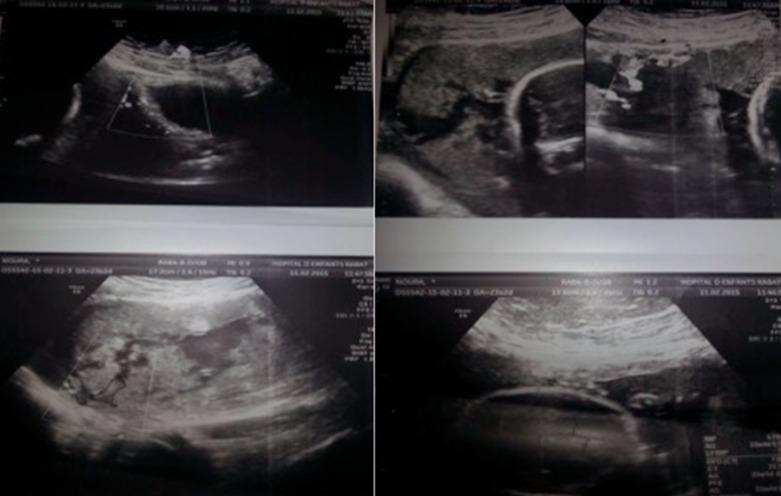

Placenta accreta spectrum disorders is a rare pathology but the incidence has not stopped to increase in recent years. The purpose of our work was the analysis of the epidemiological profile of our patients, the circumstances of diagnosis, the interest of paraclinical explorations in antenatal diagnosis and the evaluation of the evolutionary profile. We hereby report a case series spread over a period of one year from 01/01/2015 to 01/01/2016 at the Gynaecology-Obstetrics department of the University Hospital Center IBN SINA of Rabat where we identified six cases of placenta accreta. We selected patients whose diagnosis was confirmed clinically and histologically. The major risk factors identified were a history of placenta previa, previous caesarean section, advanced maternal age, multiparity. 2D ultrasound and magnetic resonance imaging (MRI) allowed us to strongly suspect the presence of a placenta accreta in a pregnant woman with risk factor(s) but the diagnosis of certainty was always histological. Placenta accreta spectrum disorders were associated with a high risk of severe postpartum hemorrhage, serious comorbidities, and maternal death. Leaving the placenta in situ was an option for women who desire to preserve their fertility and agree to continuous long-term monitoring in centers with adequate expertise but a primary elective caesarean hysterectomy was the safest and most practical option. Placenta accreta spectrum disorders is an uncommon pathology that must be systematically sought in a parturient with risk factors, to avoid serious complications. In light of the latest International Federation of Gynecology and Obstetrics (FIGO) recommendations of 2018, a review of the literature and finally the experience of our center, we propose a course of action according to whether the diagnosis of the placenta is antenatal or perpartum.

胎盘植入谱系疾病是一种罕见的病理情况,但近年来其发病率一直在上升。我们这项工作的目的是分析我们患者的流行病学特征、诊断情况、产前诊断中辅助检查的意义以及病情发展情况的评估。在此,我们报告一组病例系列,时间跨度为2015年1月1日至2016年1月1日,来自拉巴特伊本·西那大学医院中心妇产科,我们在那里确诊了6例胎盘植入病例。我们选择了临床和组织学诊断均得到证实的患者。确定的主要危险因素包括前置胎盘病史、既往剖宫产史、高龄产妇、多胎妊娠。二维超声和磁共振成像(MRI)使我们能够强烈怀疑有危险因素的孕妇存在胎盘植入,但确诊始终依靠组织学检查。胎盘植入谱系疾病与严重产后出血、严重合并症及孕产妇死亡的高风险相关。对于希望保留生育能力并同意在有足够专业知识的中心进行长期持续监测的女性,可选择保留胎盘原位,但一期选择性剖宫产子宫切除术是最安全、最实用的选择。胎盘植入谱系疾病是一种罕见的病理情况,对于有危险因素的产妇必须系统排查,以避免严重并发症。根据2018年国际妇产科联合会(FIGO)的最新建议、文献回顾以及我们中心的经验,我们根据胎盘植入的诊断是产前还是产后提出了一套行动方案。